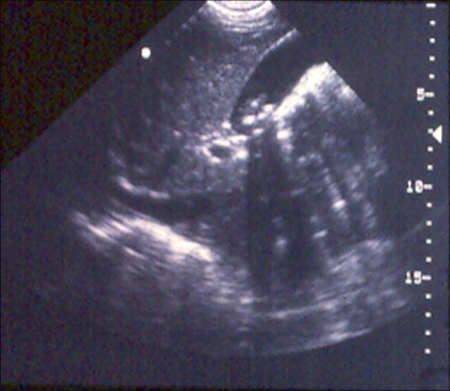

Para a colecistite aguda, a ultrassonografia abdominal tem grande sensibilidade para detectar cálculos e distensão do lúmen da vesícula biliar, além de qualquer característica inflamatória, espessamento da parede da vesícula biliar, fluido pericolecístico e/ou sinal de Murphy radiológico positivo.[84][Figure caption and citation for the preceding image starts]: Ultrassonografia de colecistite aguda e presença de cálculos biliares: a seta aponta para um cálculo no fundo da vesícula biliar, com sua sombra ecogênica abaixoCortesia de Charles Bellows e W. Scott Helton; usado com permissão [Citation ends].

[Figure caption and citation for the preceding image starts]: Ultrassonografia de vesícula biliar demonstrando colelitíase com sombreamento característicoCortesia de Kuojen Tsao; usado com permissão [Citation ends].